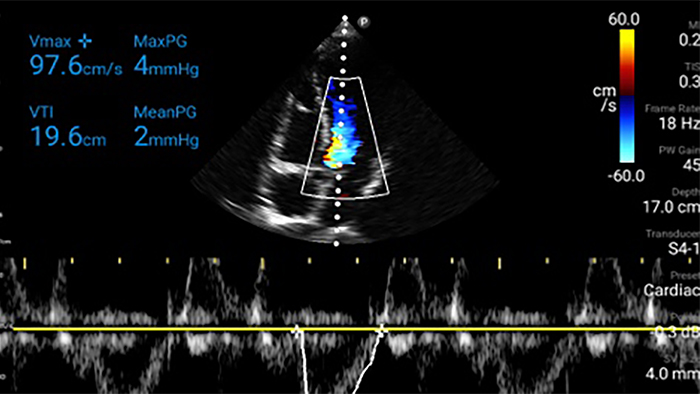

Start treatment with an accurate diagnosis

Lumify helps you see the fine details in muscles, joints, ligaments, tendons and cartilage to make a more accurate diagnosis of injuries.

Get the clarity of larger ultrasound systems with Lumify

SonoCT reinforces real tissue imaging while eliminating random artifacts. This technology produces images superior to conventional imaging in up to 94% of patients.